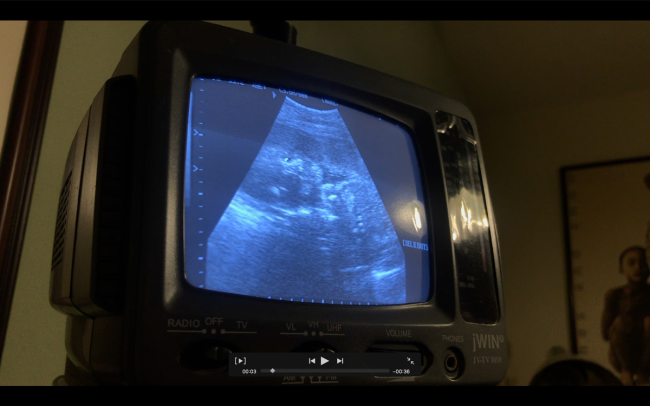

Fotografías tomadas durante la pandemia sanitaria de 2020. Por mi embarazo, tuve un encierro más prolongado debido a ser persona de alto riesgo por contagio de COVID-19. Por lo cual, imaginaba que mi bebé «flotaba» en su universo, ignorante de la época que le toco vivir.

Con el bordado, trato de recrear patrones topográficos o astronómicos, pensando que es lo que ese experimentaba dentro del útero.